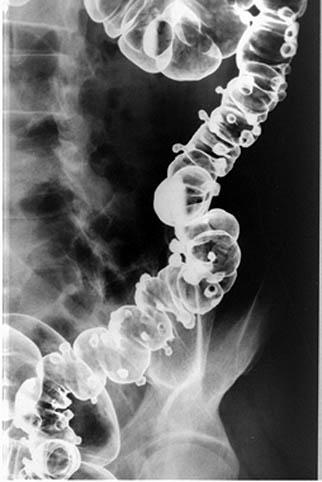

疾病(病理主体)的分类憩室/多发憩室

部位(按器官分)大肠/降结肠

检查方法X线